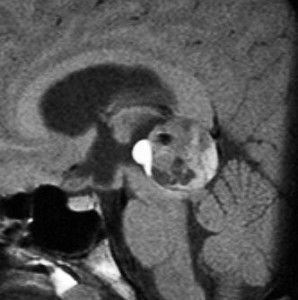

14歳の男の子です。このMRI画像はどう見ても松果体奇形腫 mature or immature teratoma 以外には考えられません。左の写真で脂肪腫が混じっていることが解ります。AFP 130 ng/ml, HCG-beta 30 mIUでしたから,ICE化学療法と放射線治療 (全脳室 25.2グレイ/15分割と局所28.8グレイ,1回線量1.8グレイ)をして少し小さくして(右の写真)から開頭手術しました。全摘出して病理診断は成熟奇形腫でしたが,治療前にはおそらくもっと未熟な部分が混じっていたと考えられます。